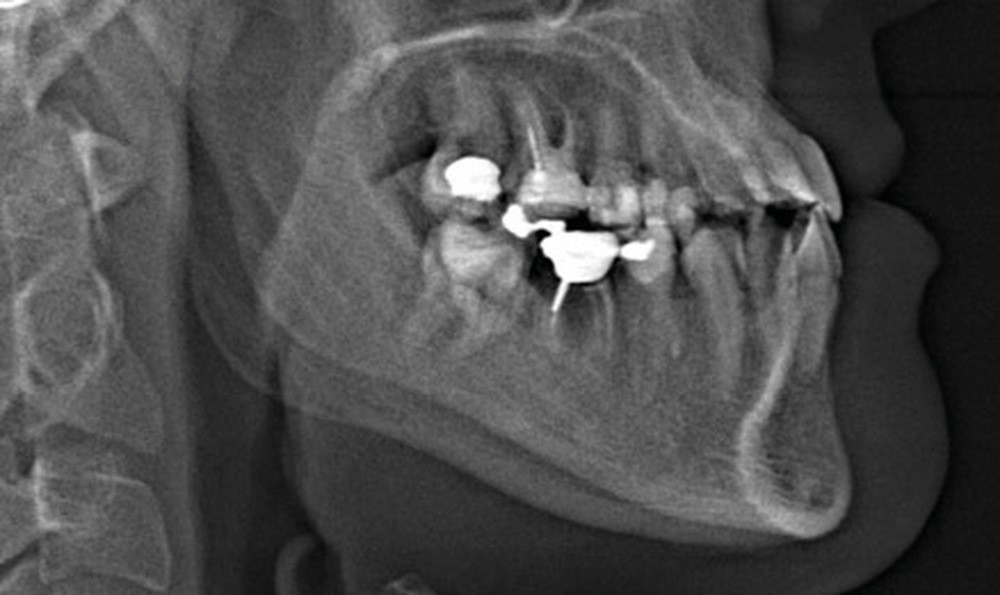

Diagnostic (fig. 1a-g)

La patiente présente une classe III squelettique dans un contexte hyperdivergent associée à une endoalvéolie maxillaire, un articulé inversé antérieur, une rétroversion incisive maxillaire, des rapports de classe I canine bilatérale, une absence de 16 et 36.

Au niveau fonctionnel, il existe un pro-glissement mandibulaire et un articulé inversé antérieur. Le profil téléradiographique montre en occlusion des rapports labiaux et un profil de classe III plus marqué que sur photographies.